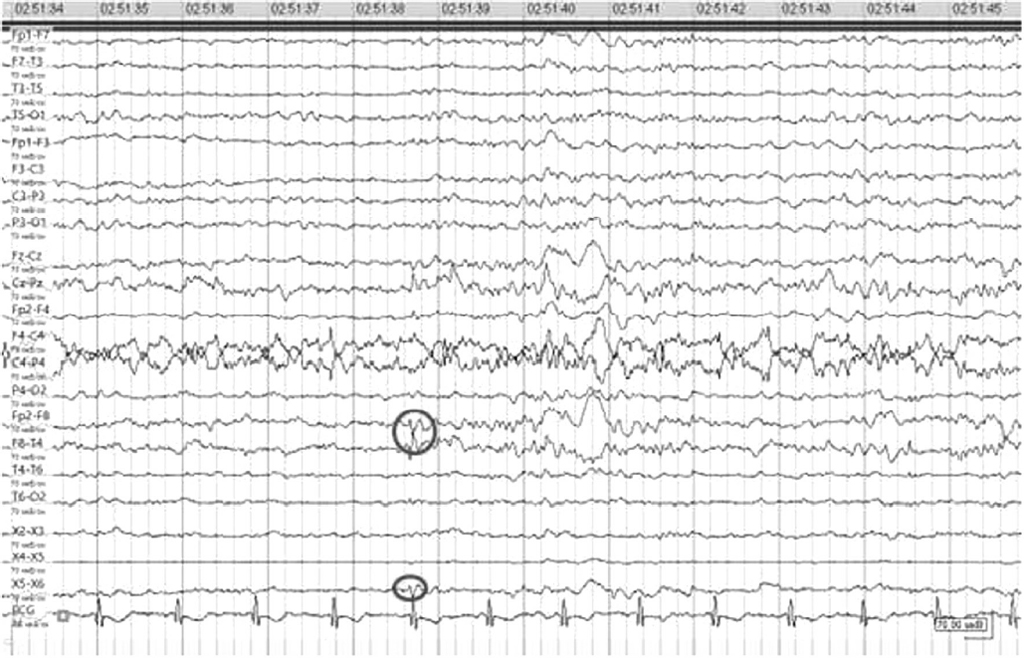

Видео-ЭЭГ-мониторинг — основной ритм по частотным характеристикам соответствует возрастной норме с отчетливым фронто-окципитальным зональным распределением, без особой межполушарной амплитудной асимметрии активности. Сон носил циклический характер, модулирован по фазам и стадиям, физиологические паттерны сна выражены удовлетворительно.

Региональные изменения в височных отделах справа в виде периодического и продолженного иррегулярного тета-дельта замедления активности, на фоне которого регистрировались эпизодические субклинические эпилептиформные разряды комплексов острая –медленная волна. Индекс представленности в записи 1–3 %.

Эпилептических приступов, паттернов эпилептических приступов в ходе исследования не зарегистрировано (рис. 2).

Рис. 2. Региональные изменения в височных отделах справа в виде периодического и продолженного иррегулярного тета–дельта замедления активности, на фоне которого регистрировались эпизодические субклинические эпилептиформные разряды комплексов острая – медленная волна. Индекс представленности в записи 1–3 %